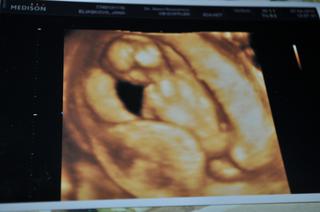

info ke kontrole...prďolka má 8,19cm ,takže se mi týdny posunuly na 14+0, TP dle utz posunut na 5.10.,ale nechá to prý na mé dr.zítra,ať se rozhodne, vše je tam,kde má být a hlavně...vrozené vývojové vady VYLOUČENY!!! 😵 😵 Ježiš, jak mě spadl kámen ze srdce....akorát,že mimčo se natáčelo pořád zády a vrtělo se,takže nějaké dvě hodnoty mi ani nezměřila, ale důležité je,že tam je i nosní kůstka i šíjové projasnění....ze 3D utz máme krásnou fotečku profilu zezadu 😀 😀 ...prostě se nenatočilo...a to dr.říkala,že jídlo mimča vždycky vzbudí...no tak to moje mimi asi segedín nenadchl 😀 ,takže se neobtěžovalo pohnout...slyšeli jsme i srdíčko ...a manža byl z toho krásně unešený 😎

tady je fotka toho našeho modela 😀 prostě se neukáže....asi slyšelo,že chci překvápko,tak neukáže ani obličejík,abych měla překvápko se vším všudy 😀

jen pro upřesnění,to co vypadá jako dvě půlky 😀 jsou pokrčené nožičky 😉 ...jsem si dělala srandu, že na nás vystrkuje zadek už od mala 😀